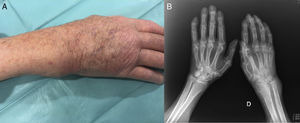

The patient was an 85-year-old man with a history of hypertension, dyslipidemia and ischemic heart disease, who had undergone revascularization for unstable angina in 1985 by double coronary artery bypass. He received standard treatment con amlodipine, atorvastatin, pentoxifylline, telmisartan/hydrochlorothiazide, omeprazole, tramadol and acetylsalicylic acid. He was referred to rheumatology because of the suspicion of severe arthritis of right wrist, with no history of a traumatic injury (Fig. 1A). Physical examination revealed a soft tissue mass in the medial ulnar fossa. It was swollen, tender on palpation and mobile. The patient did not have fever, lymph node involvement or complain of changes in his general state. Bilateral radiographs of the hands confirmed diffuse osteopenia, narrowing of the carpal and midcarpal joint space and erosion of the distal ulna and of the styloids, as well as generalized vascular calcifications (Fig. 1B).

(A) Image of the patient's right wrist. Soft tissue mass located in the region of ulna that responded to pressure and was mobile. (B) Plain bilateral radiographs of the hands. Generalized osteopenia, reduction of the joint space in right wrist. Thickening of soft tissue most evident in the region of the ulnar styloid. Severe distortion of the architecture of the radiocarpal joint and ulnocarpal fossa.